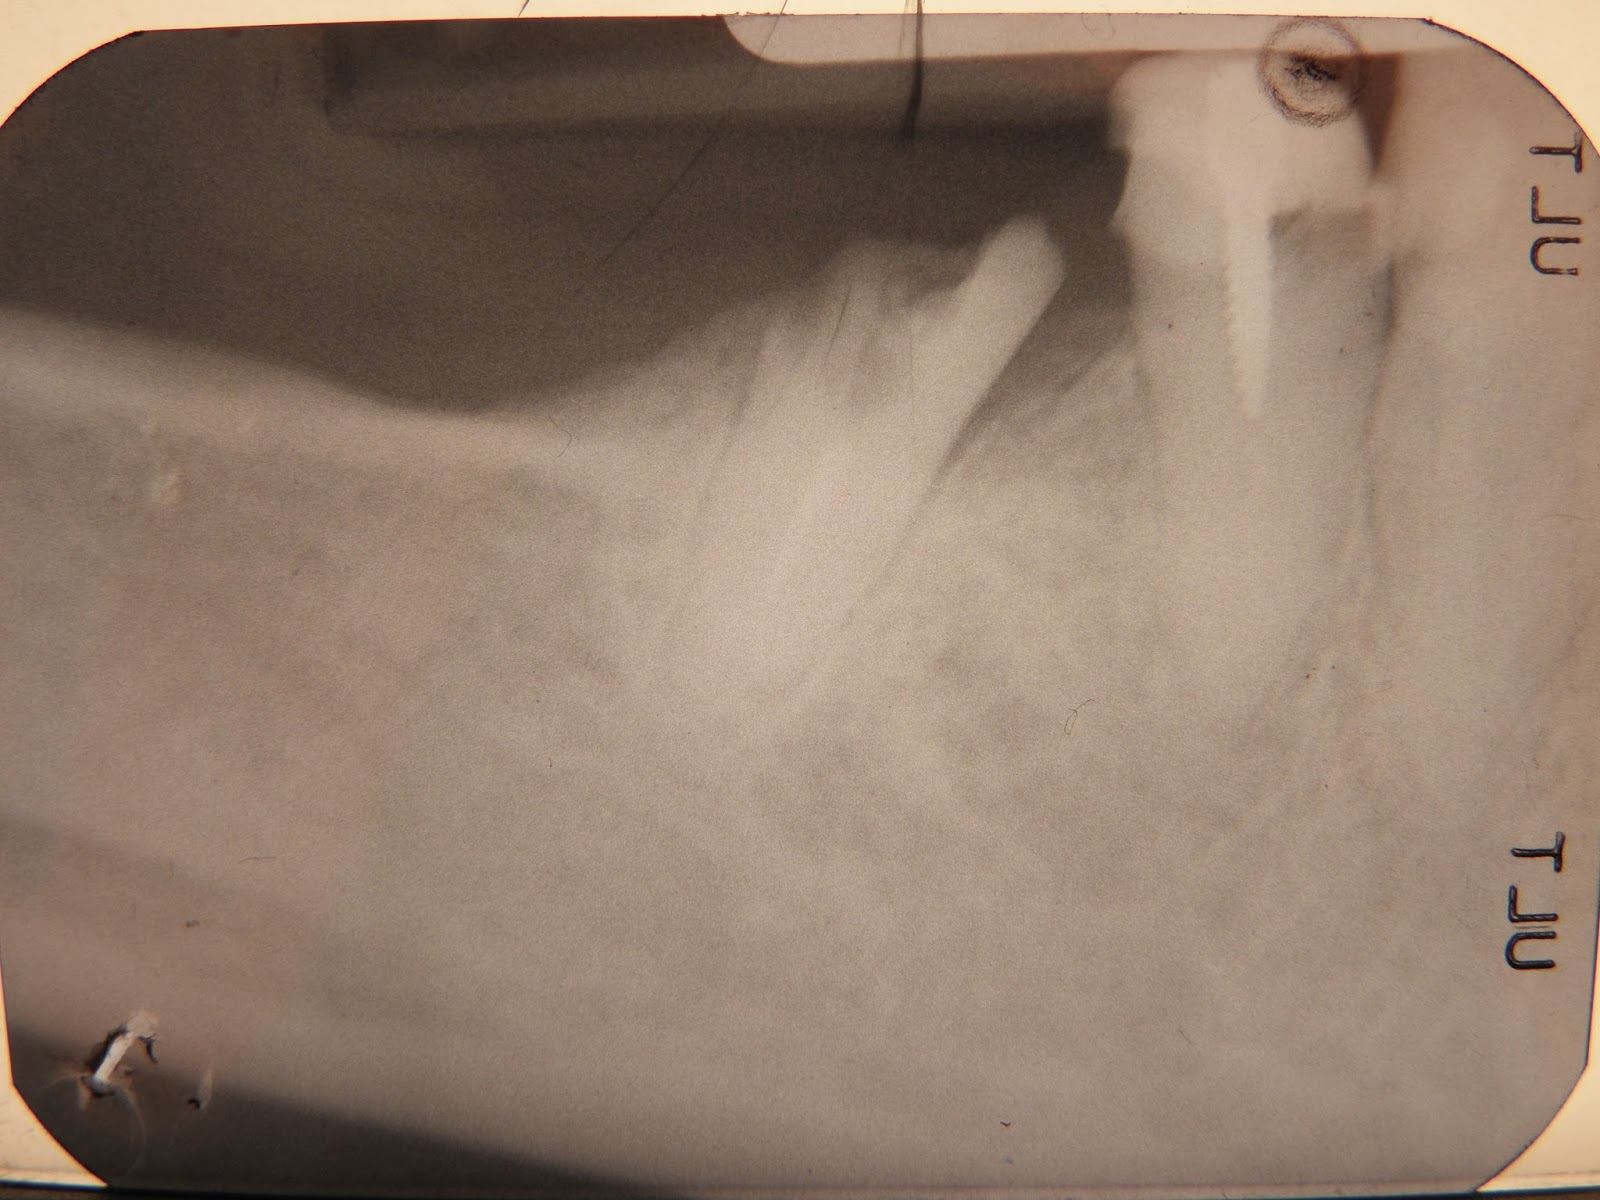

07 conservare con endodonzia e corona o estrarre?

46 fistola distale canali necrotici e calcificati

così appare il dente nel suo aspetto misero vettore d'infezione nell'organismo ed estrema fragilità tenendo conto che la parte mesiale è una vecchia ricostruzione in amalgama II classe di Black

l'estrazione atraumatica con la separazione delle due radici

così appare il dente nel suo aspetto misero vettore d'infezione nell'organismo ed estrema fragilità tenendo conto che la parte mesiale è una vecchia ricostruzione in amalgama II classe di Black

l'estrazione atraumatica con la separazione delle due radici